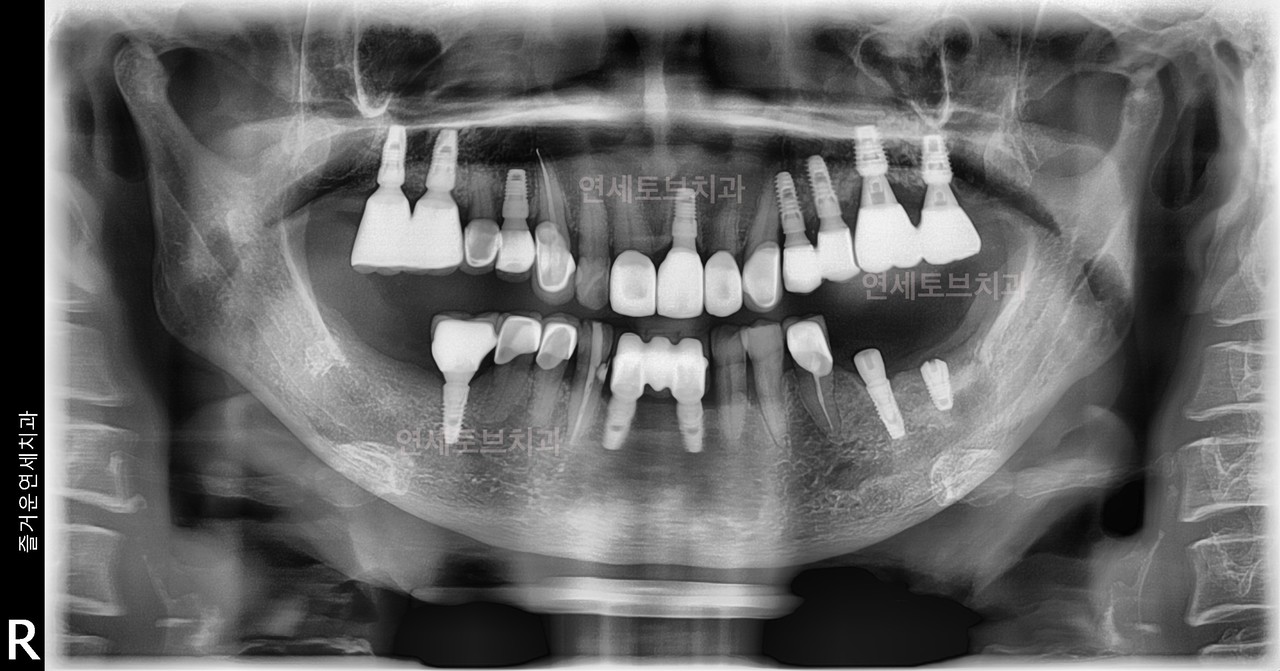

#1

#2

#3

#4